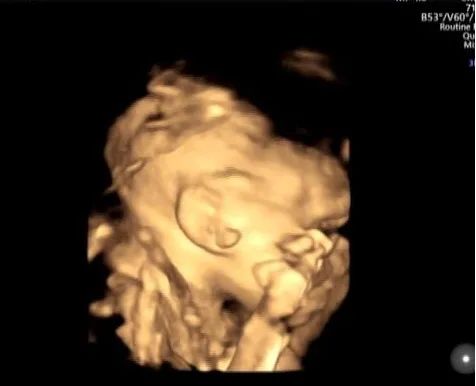

面横裂

孕妇 XXX 女 28 岁 G1PO 孕 25W1D

在我院行四维超声时发现右耳及右侧面颊部见赘生物,右侧口角增大,考虑面横裂。跟家属告知情况后孕妇继续妊娠至足月娩出一女婴,Apgar 评分:10 分,生后右侧可见附耳,右侧口角增大,其旁见赘生物,证实了产前的面横裂的诊断。

面横裂又称为巨口症,是由于第一鳃弓上颌突及下颌突融合异常所致面横裂可为单侧裂,表现为两侧口角不对称;也可为双侧裂。除口颊畸形外,还可伴第一腮弓的发育畸形,如颜面部一侧发育不良、耳前瘘管以及附耳等畸形。发生率在 1/3000~1/5000。

产前超声诊断面横裂非常困难,特别是Ⅰ级面横裂更难发现,大多数病例都是生后发现。单纯面横裂可以在孩子三个月以后通过手术治愈,预后佳。